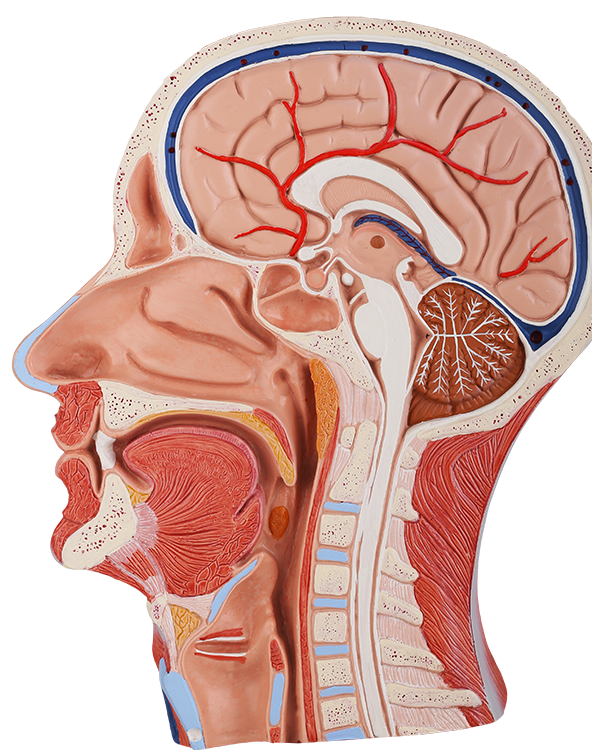

Oral & Maxillofacial Surgery

An oral and maxillofacial surgeon (OMS) focuses on treating diseases, injuries, and defects in the head, neck, face, jaw, and mouth.

OMS specialists are surgically trained in hospital residency programs, so they have unparalleled experience in a number of conditions.

Treating a Broad Spectrum of Conditions CONCERNING THE HEAD, FACE, MOUTH & JAW

What are the advantages of seeing an OMS?

Superior Surgical Skill FOR SAFE, PRECISE TREATMENT

The Value of Expert Surgical Care

“Your oral and maxillofacial surgeon (OMS) has the specialized education and training in the complexities of the bone, skin, muscles and nerves involved, to ensure you get the best possible results. “American Association of Oral and Maxillofacial Surgeons